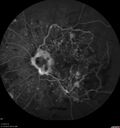

Branch Retinal Vein Occlusion - Both Eyes - Edema OD and NVE OS - Severe Non-perfusion Both Eyes324 views83 year old man with vision loss for 3 months not sure which eye. VA 20/100 OD and 20/50 OS. Tried avastin once without much improvement in the right eye and then lost to follow-up. FA in the left eye shows leaking NVENov 30, 2020

|

Branch Retinal Vein Occlusion - Both Eyes - Edema OD and NVE OS - Severe Non-perfusion Both Eyes369 views83 year old man with vision loss for 3 months not sure which eye. VA 20/100 OD and 20/50 OS. Tried avastin once without much improvement in the right eye and then lost to follow-up. FA in the left eye shows leaking NVENov 30, 2020